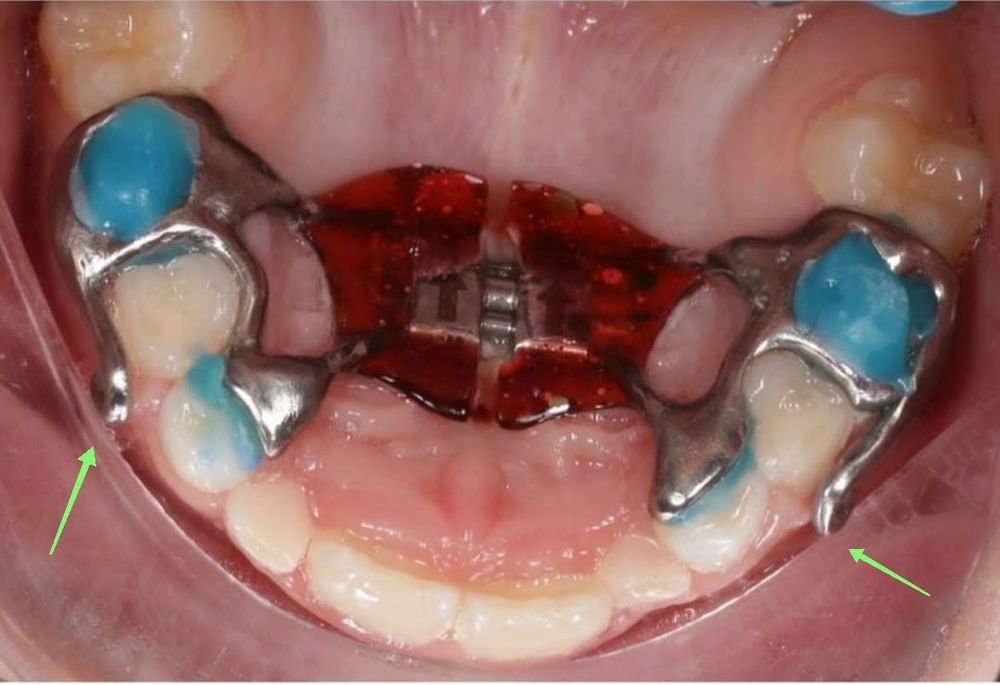

Ксюша, посмотрите, пожалуйста. Добавила фото.

Secrets_of_the_rain, у нас их не было🤷🏼‍♀️ десна вряд ли привыкнет, я бы записывалась к ортодонту на коррекцию Изображение

Ксюша, у нас их, видимо, добавили для ношения лицевой маски, чтобы нижняя челюсть не заходила на верхнюю. Я сама сейчас только увидела. Вот и думаю, что к такому вряд ли можно привыкнуть(((. Спасибо за ответ!

VER4EVI4, я просто боюсь, что крючки как-то так сделаны, что натирают десну и к этому нельзя будет привыкнуть. На остальные части аппарата жалоб нет. Именно на боль в дёснах, где соприкасаются крючки. У вас аппарат с крючками был или без?